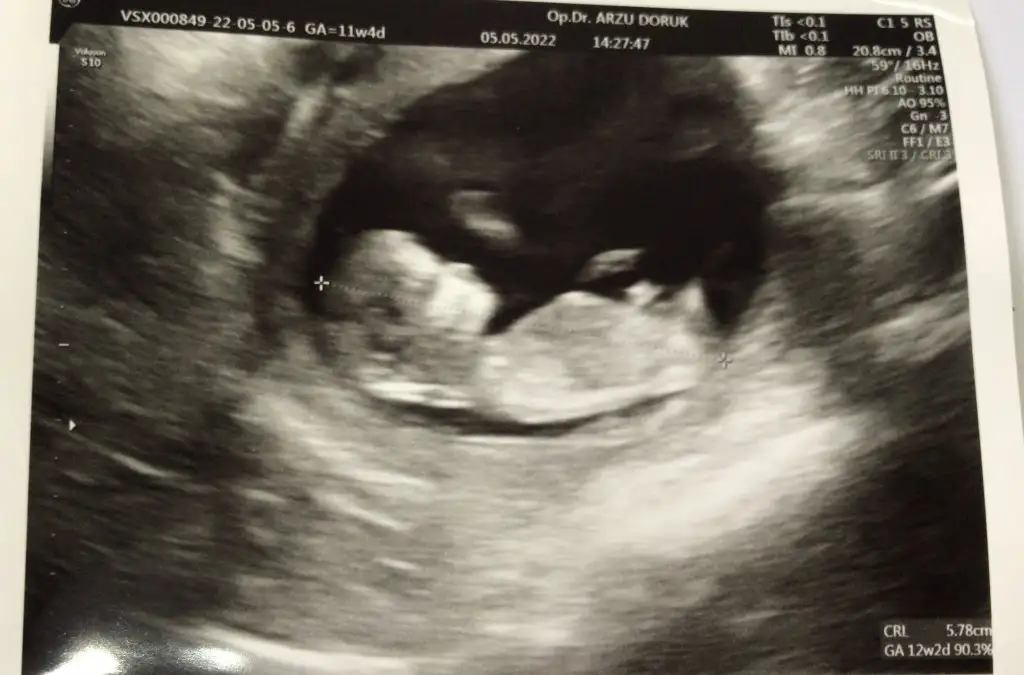

Kızlar merhabalar , bana da tahmin yapabilirmisiniz :) ve neye göre söylüyorsunuz onu da çok merak ediyorum yazarsanız çok sevinirim :) 11+4 üz

Eklentiler

• 6752E299-E085-4717-9F96-C78071E25EEC.webp

6752E299-E085-4717-9F96-C78071E25EEC.webp

32,9 KB · Görüntüleme: 142